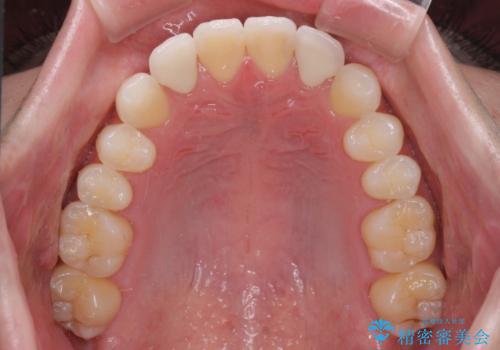

ホワイトニングを併用し、治療前と比べて自然でとても明るい口元となりました。